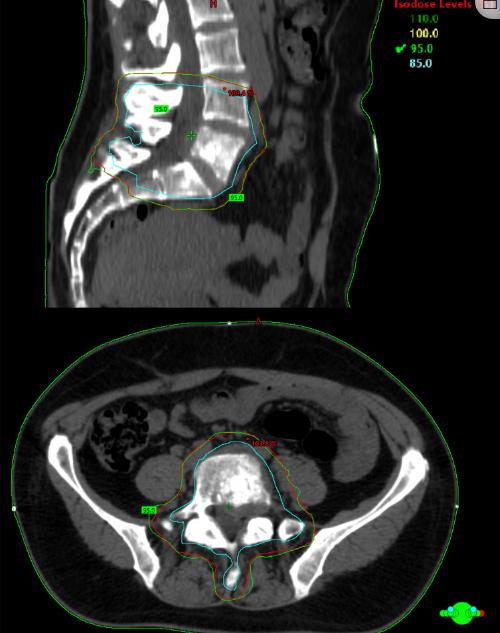

由于PET/CT未发现其他受累区域,L5的病变被认为是原发性骨肿瘤。考虑到全身治疗意义不大,多学科小组决定先用新辅助放疗,然后手术治疗。由于肿瘤种植的高风险,因此不采用最初的减压手术。此外,考虑到接近马尾和神经根,脊柱辅助放疗中的总剂量为50Gy要比(60-70Gy)更安全。在CT模拟后,GTV(肿瘤总体积)被描绘为包含整个L5椎骨,包括肿瘤的软组织成分;向上和向下进行2 cm的CTV(临床目标体积)扩张,包括邻近的骨结构;而PTV(计划目标体积)是通过从CTV延伸8 mm的等距边缘获得的。从2021年5月3日至2021年6月4日,使用IMRT进行放疗,总剂量为50 Gy,分为25次,每天2 Gy,无间断(图10)。

图10、显示CTV(蓝色)和PTV(红色)以及95%等剂量线的放射治疗计划